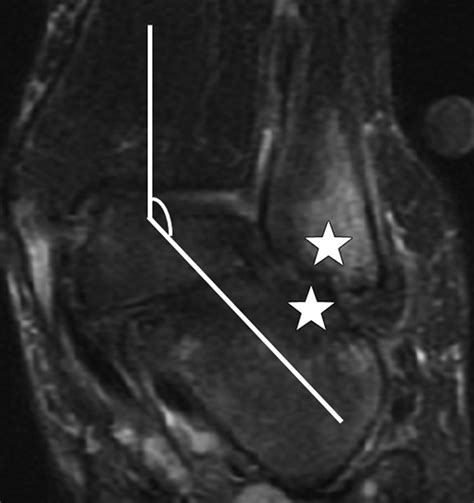

Magnetic Resonance Imaging (MRI) Offers detailed images of the bone marrow and surrounding tissues, making it the gold standard for diagnosing bone marrow edema.